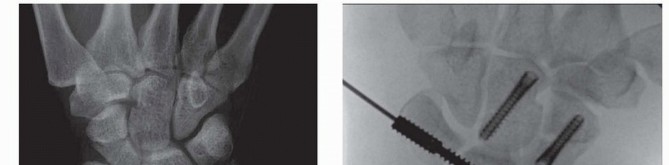

| Timing of ▪ Arthroscopically assisted reduction of distal radius fractures is most ideal reduction between 3 and 10 days following injury. Assisted fixation before 3 days usually is complicated by bleeding that can obscure visualization. Percutaneous fracture reduction more than 10 days after the injury is exceedingly difficult and often unsuccessful due to early bony healing. Arthroscopic ▪ It is important to take the time to thoroughly irrigate and débride the joint of visualization hematoma and debris. This especially helps visualization of fragment rotation. Irrigation through a separate 6U inflow portal is helpful. A Coban wrap (3M, St. Paul, MN) may be placed around the forearm to limit fluid extravasation into the soft tissues. Instrumentation ▪ Large joint instrumentation will damage the articular cartilage and is not appropriate. A mobile traction tower is extremely helpful in arthroscopic-assisted management of distal radius fractures. | Fixation ▪ Do not accept poor fixation just to treat the patient arthroscopically. Fixation should be chosen to fit the personality of the fracture. For example, K-wires should not be used to stabilize a volar Barton fracture when volar plate stabilization is the obvious superior choice. Although K-wires are easy to insert, they hinder rehabilitation and have the potential for pin tract infections. 1. Cannulated screws are recommended when arthroscopically stabilizing a fracture of the distal radius without metaphyseal comminution. 2. Multiple carpal fractures and ligamentous injuries may be treated during the same procedure ( FIG 3A,B). 3. Volar plate fixation is recommended when metaphyseal comminution is present. 4. Arthroscopic evaluation of the wrist while the distal screws of the volar plate are being placed offers the advantage of seeing the screws penetrate into the fracture fragments, thereby ensuring stability. Arthroscopic evaluation is helpful in variable-angle volar locking plates to ensure the screws do not violate the joint. Observation ▪ It is imperative following arthroscopically assisted reduction of the distal radius in the radiocarpal space to evaluate the midcarpal space. The midcarpal space is the most sensitive and ideal location to evaluate intercarpal stability. In addition, loose bodies from the capitate or hamate occasionally are seen, particularly in association with lunate diepunch fractures. Arthroscopic evaluation also aids in determining when to fix the ulnar styloid.

### FIG 3 • A. AP radiographic view showing three-part intra-articular distal radius fracture along with an obvious transverse scaphoid fracture. A more subtle capitate fracture is also seen. B. An intraoperative PA radiographic view is seen. The patient required two Acutrack (Acumed, Hillsboro, OR) cannulated compression screws for repair of the distal radius fracture. The capitate and scaphoid were likewise repaired using Acutrack cannulated screws. Intraoperatively, a lunotriquetral ligament tear was seen and the interval stabilized with an Acumed Scapholunate Intercarpal (SLIC) screw (Acumed).